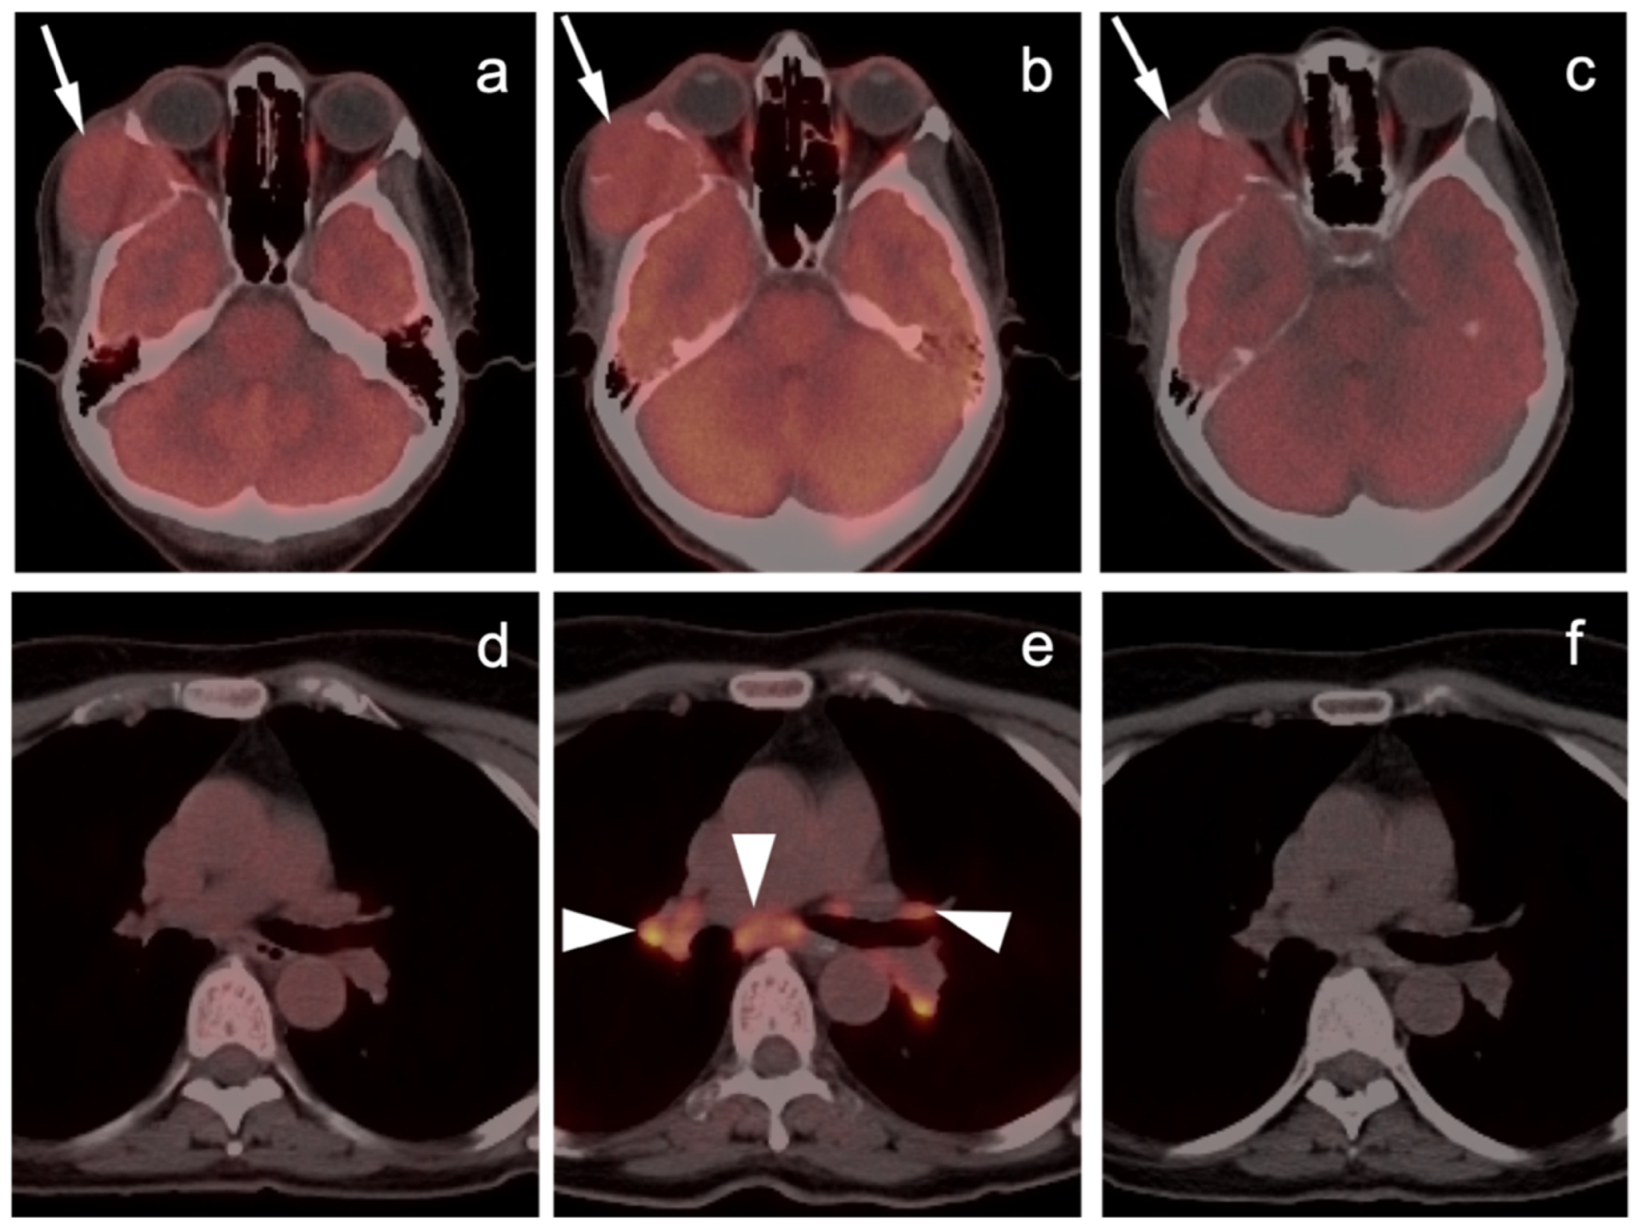

2.2. Challenges Related to Immunotherapy

2.3. Melanoma

2.3.1. Cutaneous Melanoma

2.3.2. Ocular Melanoma

2.3.3. Mucosal Melanoma